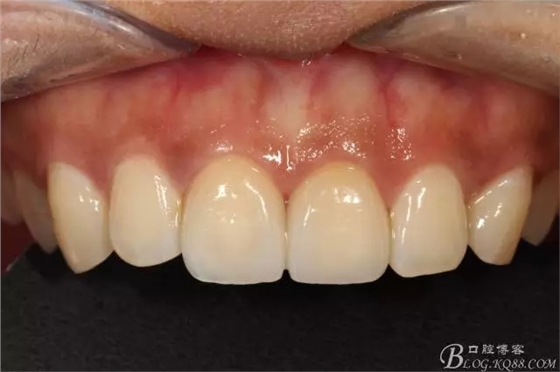

粘接完成即刻照

即刻照局部放大

兩周后復(fù)查(訴11遇冷有點(diǎn)不適,因11備牙有點(diǎn)多,露牙本質(zhì)。囑注意不要進(jìn)食過冷過熱食物。癥狀約一個(gè)月后逐漸消失。)

兩周復(fù)查局部放大